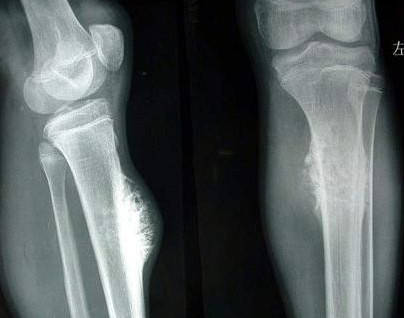

骨癌是發生在骨骼以及附屬組織的惡性腫瘤,侵犯性強且容易出現轉移,一般早期骨癌患者帶有局限性,癌細胞未出現轉移和擴散,及時采取根治性手術切除,必要時候術后可進行一段時間的放療、化療,治愈可能性還是比較高的。

骨癌能治愈嗎骨癌早期有較大幾率能治愈,中晚期患者則難度較大,治療目的主要是延長生存周期。對于比較小的骨癌,臨床上多選擇根治性切除,如果比較大,可考慮先行化療和放療,再進行手術,降低復發,盡可能保證患兒患肢功能。